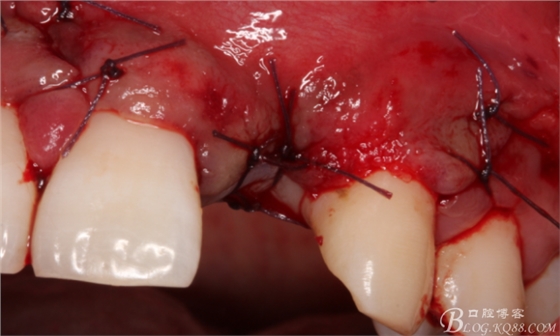

縫合。

4個(gè)月后,唇側(cè)豐滿度尚可,與鄰牙之間齦乳頭完整。